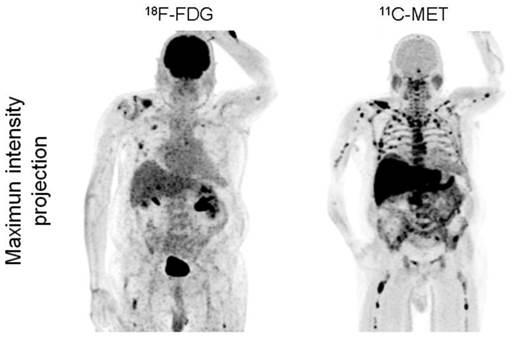

Imaging with MET demonstrated more focal lesions than FDG in 28/43 patients (65.1%, p<0.001). In the remaining patients, an equal number of MM manifestations were detected with both tracers. Most of the lesions exclusively identified by MET located within the bone marrow compartment (28/28; 100%) and in the appendicular skeleton (24/28; 85.7%; figure 2).

Display of a patient (patient #1) with newly diagnosed MM Ig G κ. FDG depicts faint to moderate uptake in the skeleton in contrast to highly intense lesions in MET, e.g. in the right clavicle. Multiple additional intramedullary lesions are clearly detected by MET.